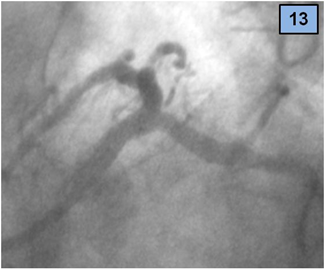

5. The procedure was successfully terminated (final TIMI 3 flow) by kissing balloon dilatation of both branches, with two non-compliant NC balloons of 3.5 x 12 mm (Figure 12). Figures 12 and 13 show the final result.

Figure 13 Final result, LAO caudal view.